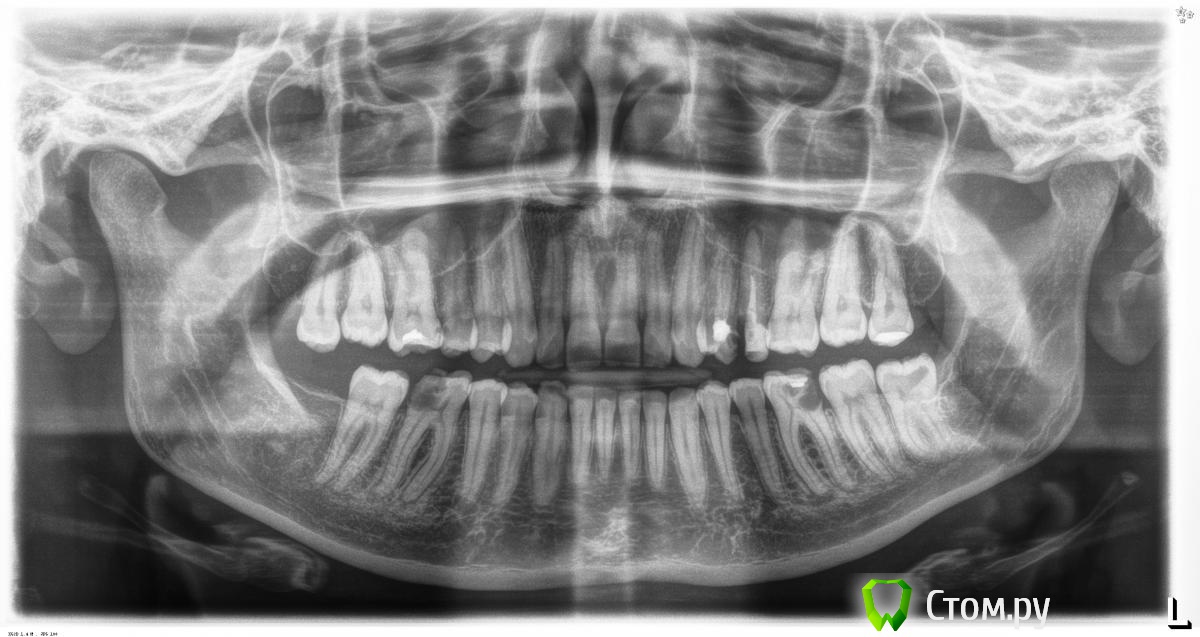

Shaid Опубликовано 28 января, 2014 Поделиться Опубликовано 28 января, 2014 Здравствуйте, уважаемые коллеги! Читаю форум с сентября 2011 года по настоящее время. За это время узнал больше, чем за всю учебу в ВУЗе. До сих пор не решался выложить что-либо на ваш суд. Но надо развиваться дальше и то подтолкнуло меня на создание данной темы, в которой я буду выкладывать удачные и не очень случаи из моей практики.Буду благодарен за любую критику. Итак, неделю назад пришла пациентка с желанием "подлечить все". После ОПТГ было решено начать с 4.6 зуба(кроме того, этот зуб начали лечить месяц назад, положив мышьяк, но не долечили). Глянув на снимок и ужаснувшись от длины корней этого зуба(30 мм по замерам оптг), я начал лечение, в первое посещение - ампутировал(да-да, он был живой несмотря на рентгенологич.картину) пульпу и создал доступ в каналы, сделал билд-ап из Vitremer. Во второе - первично прошел каналы и поставил Метапасту(не хватило времени). В третье, сколол клампом свой билд-ап мех, мед.обр-ка Протейперами до f2 насколько хватило длины инструмента, дальше - ручные. Мыл гипохлоритом, гуттой перемешивал. Обтурация - латералка .02 конусными. 10 Ссылка на комментарий

Shaid Опубликовано 4 мая, 2014 Автор Поделиться Опубликовано 4 мая, 2014 (изменено) Пациентов в праздники мало, сижу, балуюсь:http://imageshack.com/a/img845/5382/q7i1.jpg http://imageshack.com/a/img841/457/bo6n.jpg http://imageshack.com/a/img841/7686/2j1g.jpg Изменено 4 мая, 2014 пользователем Shaid 10 Ссылка на комментарий

Гарриевич Опубликовано 4 мая, 2014 Поделиться Опубликовано 4 мая, 2014 Отлично справились мех, мед.обр-ка Протейперами до f2 насколько хватило длины инструмента, дальше - ручные.Купите протейперы 31мм длины Ссылка на комментарий